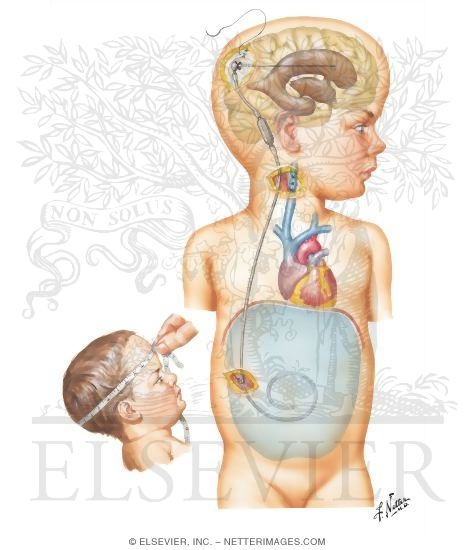

Shunt Procedure for Hydrocephalus

Hydrocephalus Is Most Often Treated By Surgically Inserting …